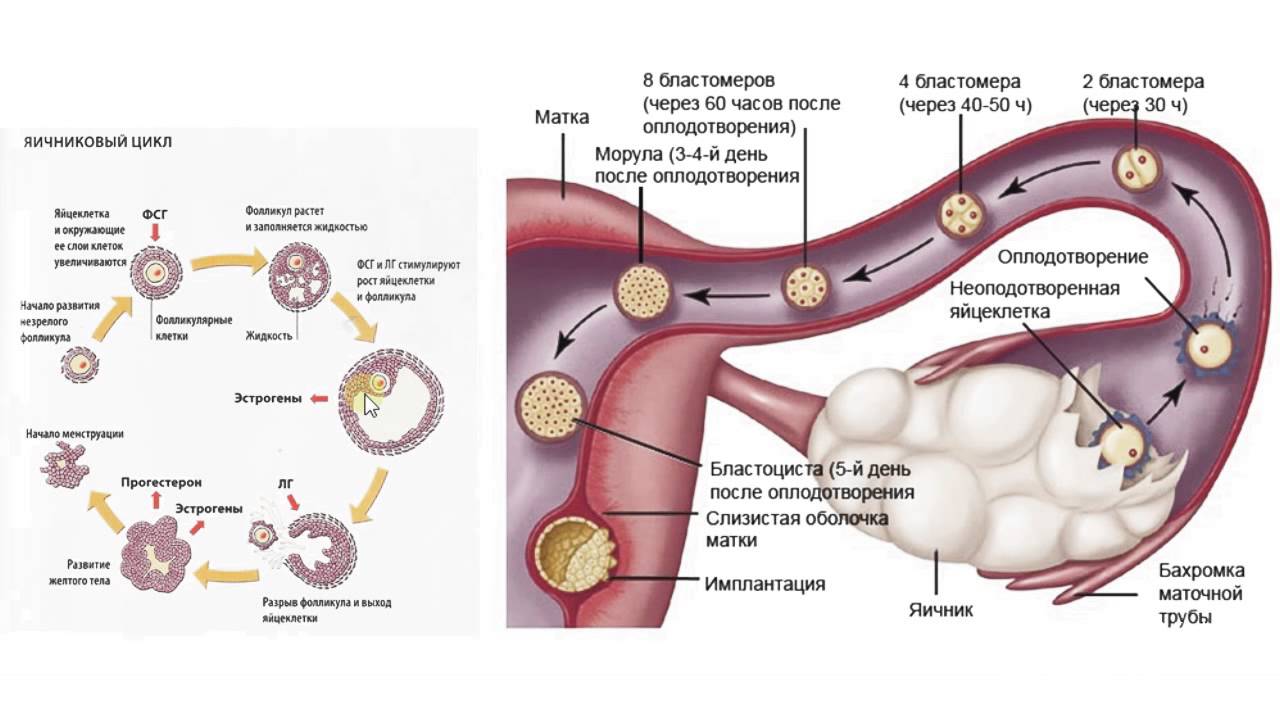

Созревание фолликула в яичнике: этапы и процессы